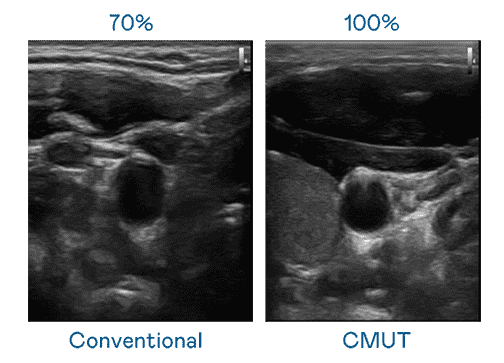

CMUT 技术是一种用电容式微机电元件来产生超音波讯号的技术。。。与传统 PZT 压电式技术相比,,,CMUT 频宽增加 30%,,更宽频的超音波讯号让影像解析度大幅提升,,是实现高影像品质医疗超音波扫描、、、、促进精准医疗发展的关键技术。。

大频宽带来超清晰影像

超音波影像的解析度高低,,首先取决于探头能发出的讯号频宽。。MG电玩 CMUT 可提供高清晰的超音波讯号,,提供高频宽、、高灵敏度、、、影像纹理细节更高的超音波影像,,,,协助医护人员缩短影像判读时间及利用精准的医疗影像进行诊断。。